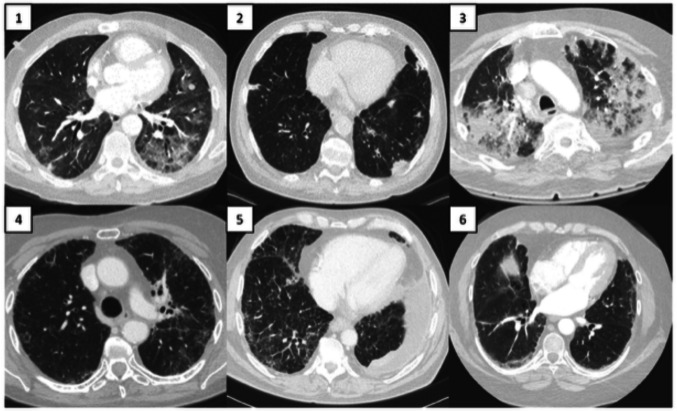

Purpose: The aim of this study is to better characterize the clinical characteristics and outcomes of patients diagnosed with Immune checkpoint Inhibitor (ICI) pneumonitis and propose predictive models.

Patients and methods: Patients diagnosed with ICI pneumonitis at Mayo Clinic from 2014 to 2022 were studied. All cases were independently reviewed by our pulmonology specialist (A.E.) to confirm the appropriate diagnosis. The grading of pneumonitis was defined in accordance with ASCO guidelines (Schneider et al. in J Clin Oncol 39(36):4073-4126, 2021. https://doi.org/10.1200/JCO.21.01440 ). Predictive modeling was performed using gradient boosting machine learning technology, XGBoost (Chen in 1(4):1, 2015), to conduct binary classification and model reverse engineering using Shapley statistics (Lundberg and Lee in Adv Neural Inf Process Syst 30, 2017).

Results: One hundred and seventy patients with ICI pneumonitis were included (median age 67; IQR 59, 75). Median overall survival was 2.3 years (95% CI: 1.8, NR). A higher grade of ICI pneumonitis was associated with inferior survival (HR 5.85, 95% CI: 2.27, 15.09; p < 0.001). Patients who were rechallenged with immunotherapy had significantly improved hazard of survival compared to patients not rechallenged (HR 0.37, 95% CI: 0.21, 0.68; p = 0.001). Risk of death from ICI pneumonitis prior to starting immunotherapy was modeled with an area under the curve of the receiver operator characteristic (AUC-ROC) of 0.79 with the most contributory features including peripheral blood lymphocyte count, oxygen dependence, pulmonary function testing, and PD-L1 expression.

Conclusion: The presentation of ICI pneumonitis is highly variable, and outcomes are dependent on severity, but favor grade 2 disease when patients are rechallenged with immunotherapy. However, using commonly available clinical data, we can accurately identify patients at high risk of death from ICI pneumonitis. Further effort is needed to produce clinical models able to provide clinician decision support when evaluating patients with ICI toxicities and considering ICI rechallenge.